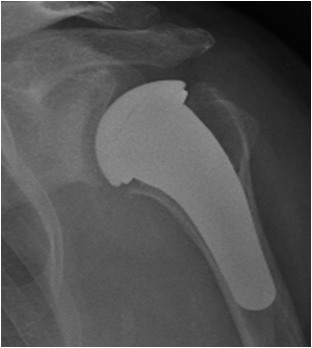

Advanced degenerative-arthritic diseases of shoulder and elbow are treated by prosthetic replacement with the aim of providing pain free movement in elderly patients or in younger patients with severe post-traumatic joint diseases.

In the latest years, articular shoulder and elbow prostheses intensely developed, with always more “anatomic” designs (that is, systems that are similar to the anatomy of the healthy joint).

The continuous research in minimally invasive and new materials development allow us, when indicated, to use implants with short stem or pyrocarbon surfaces, solutions that allow to better respect the patient's anatomy and the osteo-cartilaginous structures of the shoulder, with the aim to speed up the post operative recovery and reduce the possible complications.

Patients with an irreparable rotator cuff tear (who, until recently, have been severely limited in their activities) can today be treated with the so-called “inverse prosthesis”, which is based on the inversion of the articular surfaces shape.